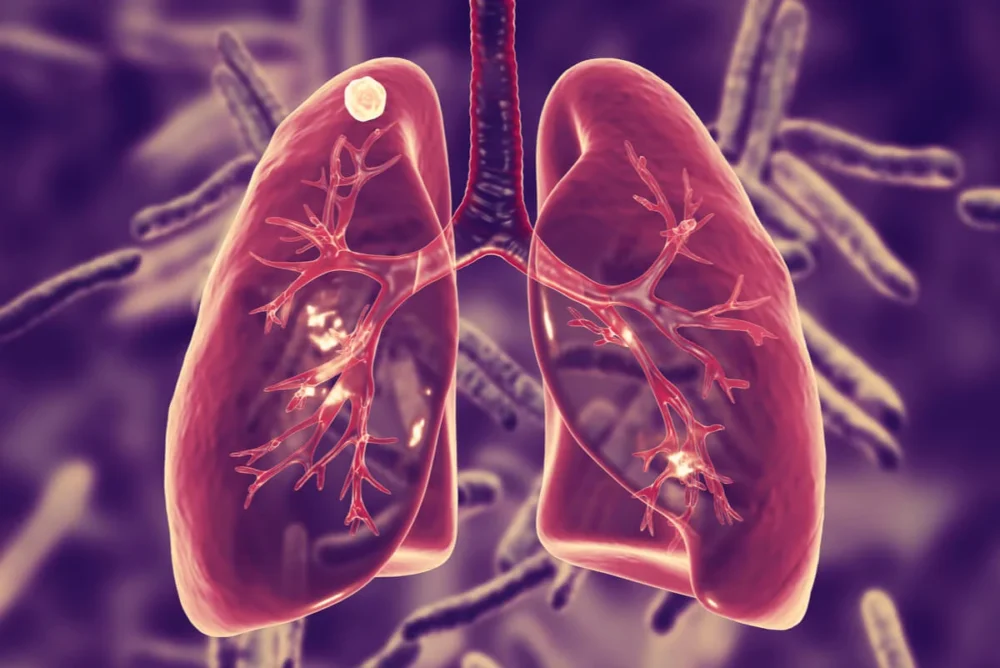

Autoridades sanitarias confirmaron un incremento reciente de casos de tuberculosis en distintas regiones del país, situación que ha encendido alertas dentro de la comunidad médica y ha motivado el refuerzo de acciones de vigilancia epidemiológica.

Las autoridades recordaron que la tuberculosis es una enfermedad transmisible que puede atenderse de manera efectiva si se inicia tratamiento en etapas tempranas. Por ello, recomendaron acudir a valoración médica ante la presencia de tos persistente, fiebre, sudoración nocturna o pérdida de peso.